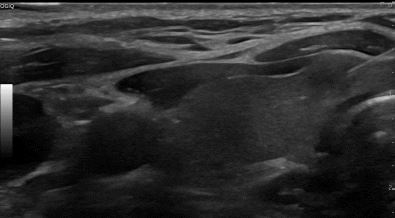

상기환자 외부건진 이상소견으로 내원하신 30대 중반 여성분으로

의심스러운 갑상선 좌엽 세포검사후 갑상선암으로 진단되었습니다